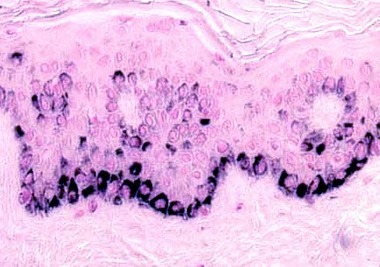

Name the stain for melanin

Fontana Masson